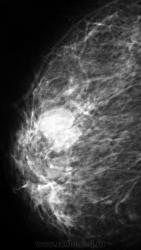

Фиброаденома или киста?

Больше похоже на кисту, но всё же поможет в диф.диагностике узи молочных желез

У меня возникло недоверие к участку, помеченному стрелками, а главное у "лучикам".

Помеченный участок, мне видится не подозрительным на neo процесс

А, я бы придралься с учетом выраженного расширения отдельного сосуда.

В другой железе так же  не большие овальные образования скорее всего кисты. По общепринятой тактике - назначается УЗИ, если простая киста - удаляется содержимое, вводится воздух(онкологом, врачем УЗИ, хирургом,  где, кто выполняет эту процедуру), далее пневмоцистография (к-к и мед -лат проекции) для подтверждения отсутствия внутриполстных образований и контроля удаления содержимого, если все нормально - наблюдение, Если при УЗИ образование тканное, или стенки кисты толстые, не равномерные, имеются внуирипролостные компоненты -  удаление с гистологией. Мелкие кисты подлежат наблюдению.

Спасибо за советы. т.е, как я понял, скиалогически предположить киста или фибрааденома, когда нет кальцификации, не представляется возможным.

Вы абсолютно правы